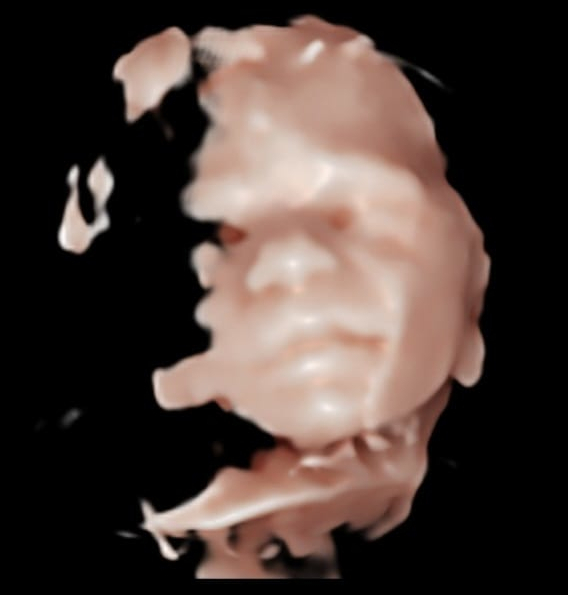

5D / HD

Facial feature scan